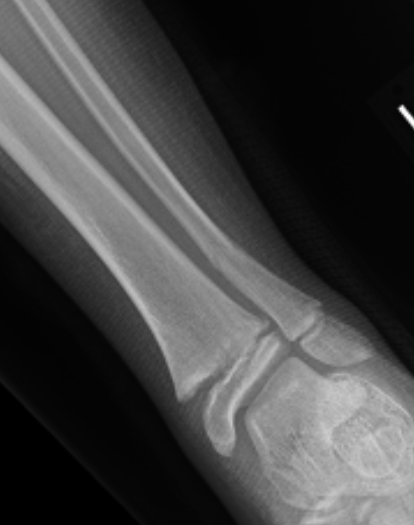

| SH I distal tibia / fibula | SH II distal tibia | SH III medial malleolus |

![]() |

| Low risk growth arrest | 40% risk growth arrest | 30% risk physeal bar |